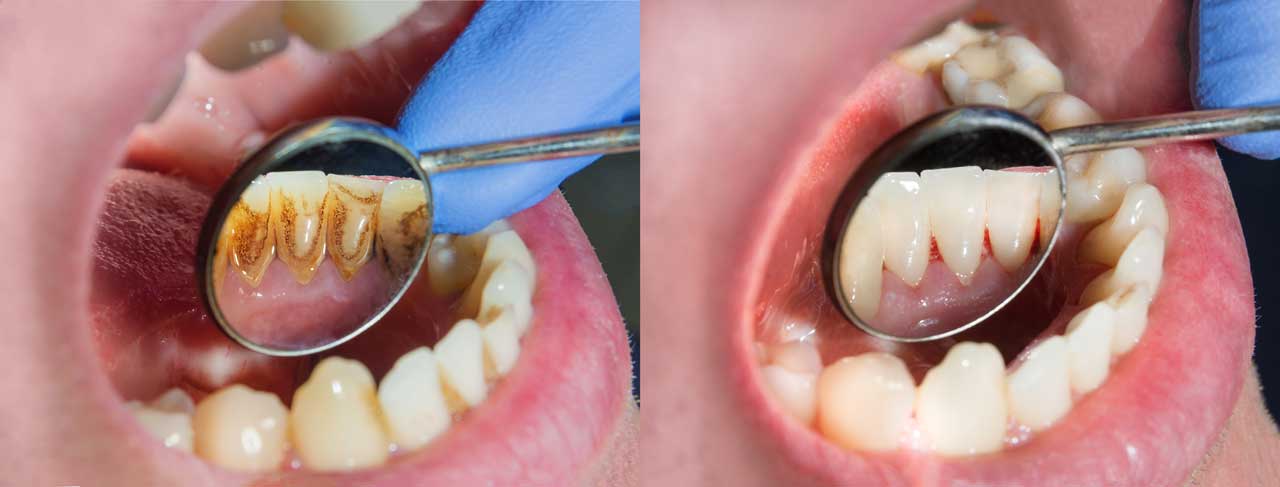

Misconception 2: "Teeth cleaning makes gaps between teeth larger."

Many people feel increased gaps after cleaning. This is actually a normal phenomenon as the gums return to their original state after the space previously occupied by calculus is cleared . The exposure of this space creates an illusion of widening gaps, not caused by the cleaning itself .